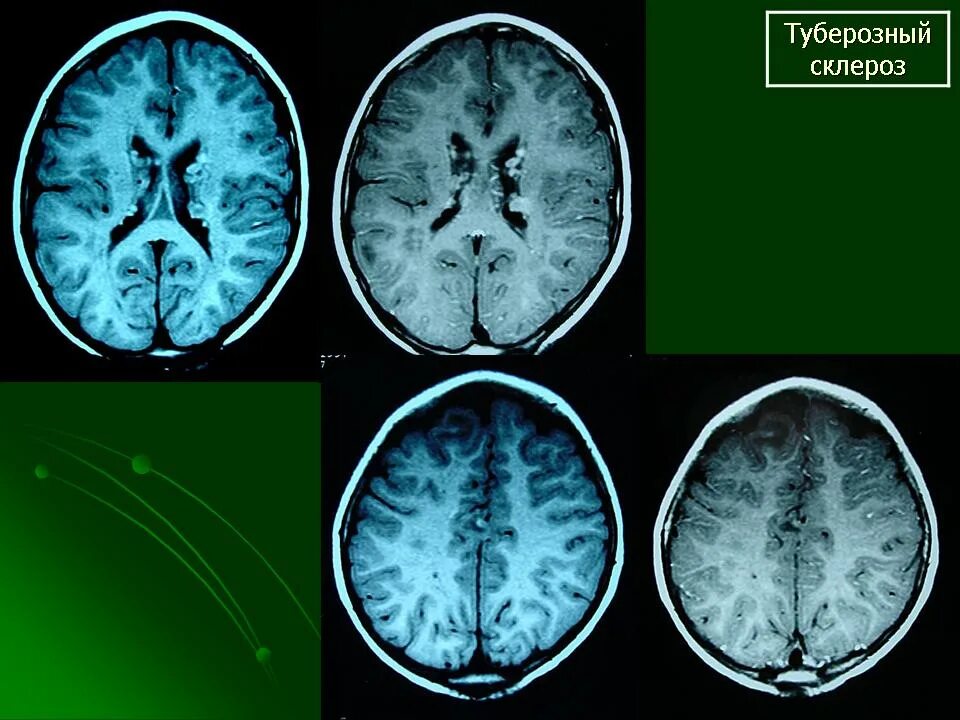

Туберкулезный склероз